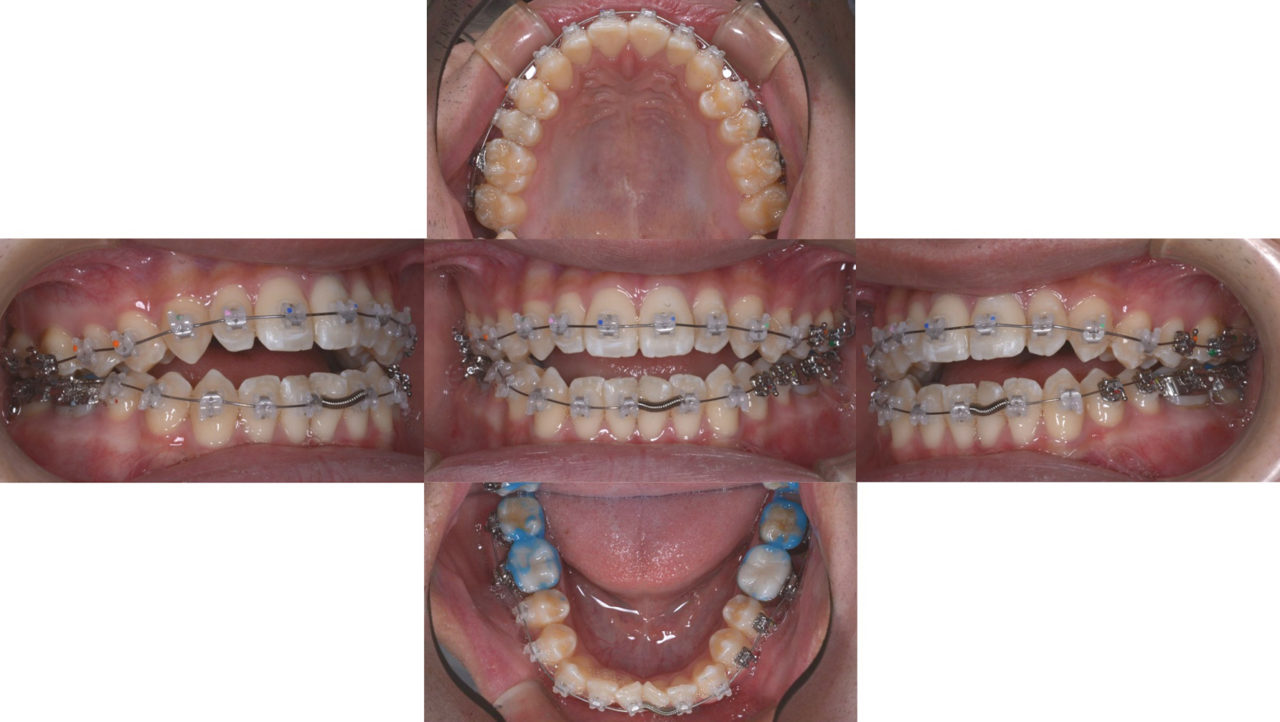

| 診断 | アングルクラスⅠの開咬 |

| 矯正方法 | 矯正用アンカーを用いた非抜歯によるマルチブラケットシステム |

| 備考 | 奥歯の痛みを主訴に来院されました。嚙み合わせの状態を見ると前歯が噛んでいない「開咬」でした。 開咬は奥歯に負担がかかる嚙み合わせで、痛みの根本原因と診断しました。 矯正用アンカーを用いて、奥歯を圧下して、開咬を治す治療計画を立てました。 開咬は後戻りしやすい病態なので、保定をしっかりしてメインテナンスをしています。 |

初診

矯正治療開始